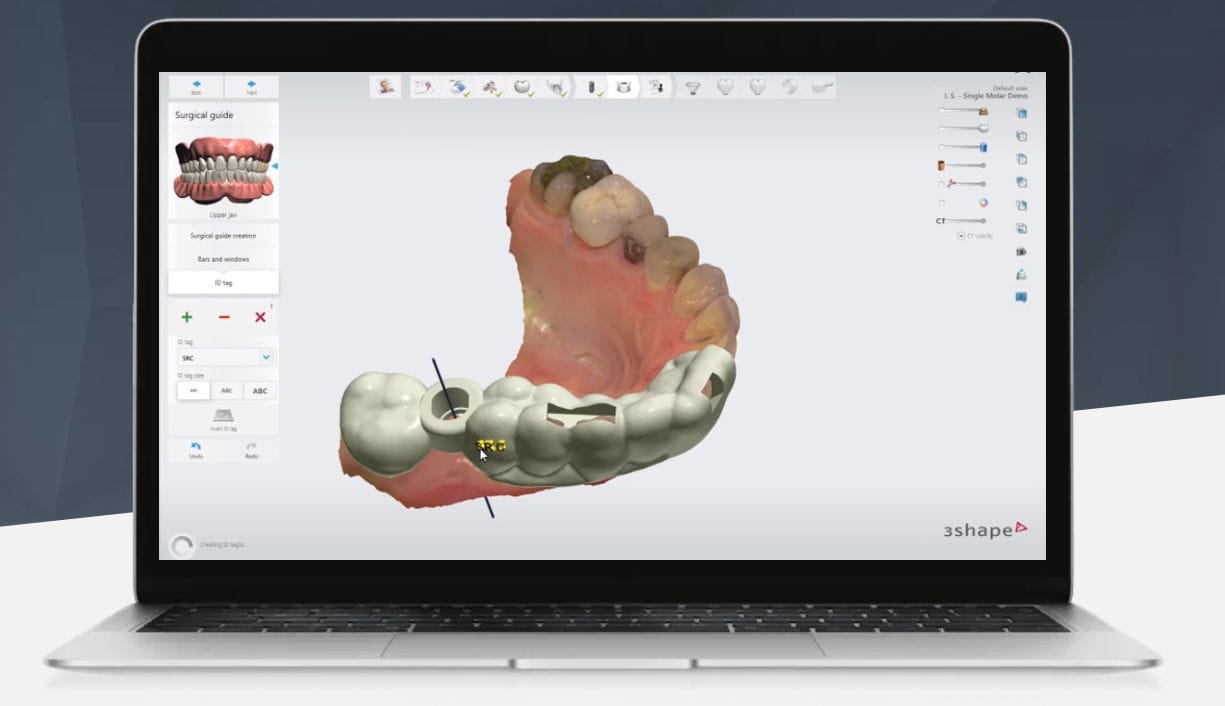

Esqueça as moldagens desconfortáveis. Utilizamos escaneamento 3D com a tecnologia 3Shape para desenhar seu novo sorriso (Implantes ou Lentes) em harmonia perfeita com seu rosto.